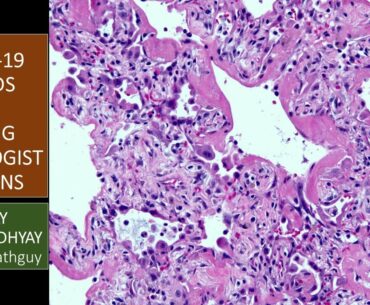

This brief video by an expert in lung pathology explains what pathologists see under the microscope in lung tissue from patients who are severely ill from viral infections such as COVID-19, which is currently causing a pandemic. See links below…